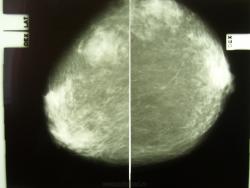

Пол пациента: Женский пол Тип патологии: Доброкачественное новообразование, киста Область исследования: Молочные железы Методы исследования: Rg Профилактическая маммография. Пациентка жалоб не предъявляет. https://radiomed.ru/sites/default/files/styles/case_slider_image/public/user/712/sl273088.jpg?itok=RtEfWYVd ID:6935 Втр, 21/09/2010 - 04:27 #1 Vikkur Не на сайте Был на сайте: 4 года 7 месяцев назад Зарегистрирован: 24.09.2009 - 14:34 Публикации: 1749 на данных снимках слева классическая фиброаденома с включением макрокальцификатов. По остальным участкам множественные кистовидные тени до 0,6 см, в заключении написал бы остаточные проявления фибрознокистозной мастопатии контроль 1 раз в год. Виктор. Втр, 21/09/2010 - 19:43 #2 Глазков Игорь А... Не на сайте Был на сайте: 9 месяцев 1 неделя назад Зарегистрирован: 19.12.2008 - 20:41 Публикации: 1597 Честно о фиброаденоме не подумал сразу. Прийди к Себе

на данных снимках слева классическая фиброаденома с включением макрокальцификатов. По остальным участкам множественные кистовидные тени до 0,6 см, в заключении написал бы остаточные проявления фибрознокистозной мастопатии контроль 1 раз в год.